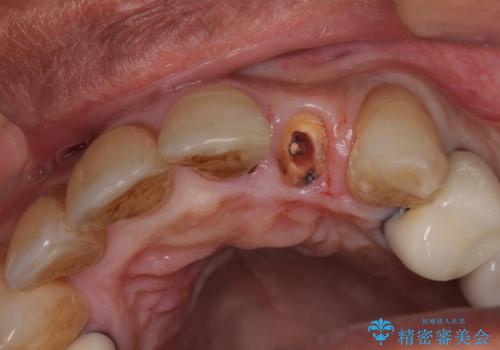

- 前歯のセラミッククランが外れてしまったとのことで来院された患者様です。

診察をしたところ、歯根に縦破折が認められ、抜歯が必要と判断されました。